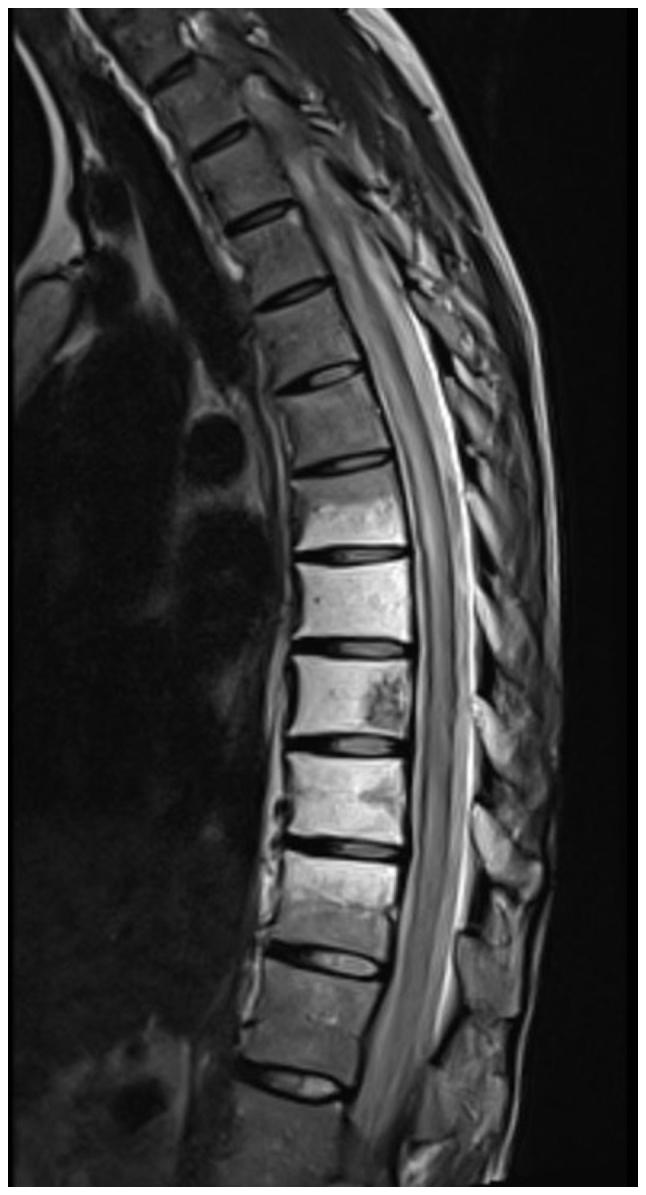

Immune checkpoint inhibitors (ICIs) have revolutionized oncology, shifting the approach from directly targeting tumor cells to enhancing the immune response of the host towards tumor cells by blocking inhibitory receptors or ligands. The present report describes the case of a 26-year-old female patient diagnosed with a rare subtype of renal cell carcinoma (RCC), transcription factor E3-rearranged (t)RCC, who presented with progressing motor weakness of the lower extremities, along with urinary and fecal incontinence, which had begun 3 days prior to admission. A diagnosis of longitudinally extensive transverse myelitis (LETM) was made, resulting in the administration of methylprednisolone and intravenous immunoglobulin. Subsequently, the condition of the patient markedly improved. LETM, a rare and potentially life-threatening condition, manifests through symptoms such as pain, sensory deficits, motor impairments and disturbances in bladder and rectal function. The positive neurological outcome in the patient in the present case underscores the significance of timely intervention. Whilst the synergistic impact of combining radiotherapy and immunotherapy in cancer treatment is widely emphasized, their influence on the spectrum and severity of toxicities remains underexplored. The present case, documenting LETM after treatment of tRCC with pembrolizumab, sheds light on a rare neurological adverse effect of ICIs. It underlines the need for prompt action in the effective management of immune-related adverse effects. Furthermore, the present case serves as a noteworthy contribution to the evolving understanding of the intricate dynamics between immune modulation and treatment-related complications in the context of innovative cancer therapies.

免疫检查点抑制剂(ICIs)彻底改变了肿瘤学,将治疗方法从直接靶向肿瘤细胞转变为通过阻断抑制性受体或配体来增强宿主对肿瘤细胞的免疫反应。本报告描述了一名26岁女性患者的病例,该患者被诊断患有肾细胞癌(RCC)的一种罕见亚型,即转录因子E3重排(t)RCC,入院前3天开始出现下肢进行性运动无力,伴有大小便失禁。诊断为纵向广泛横贯性脊髓炎(LETM),随后给予甲泼尼龙和静脉注射免疫球蛋白治疗。患者病情随后明显改善。LETM是一种罕见且可能危及生命的疾病,其症状包括疼痛、感觉障碍、运动障碍以及膀胱和直肠功能紊乱。本病例患者积极的神经学转归凸显了及时干预的重要性。虽然放疗和免疫疗法联合在癌症治疗中的协同作用被广泛强调,但其对毒性谱和严重程度的影响仍未得到充分探索。本病例记录了帕博利珠单抗治疗tRCC后出现LETM的情况,揭示了ICIs一种罕见的神经学不良反应。它强调了在有效管理免疫相关不良反应方面迅速采取行动的必要性。此外,本病例为在创新癌症治疗背景下不断发展的对免疫调节与治疗相关并发症之间复杂动态关系的理解做出了值得注意的贡献。